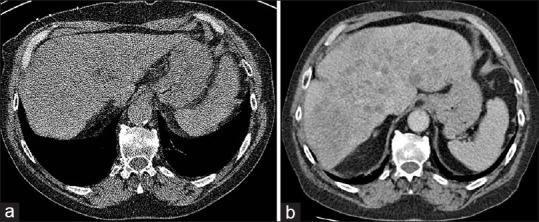

We present a case of lung cancer incidentally detected as a pulmonary nodule on computed tomography attenuation correction (CTAC) images during myocardial perfusion scintigraphy (MPS). Unfortunately, the incidental lesion was not fully investigated following MPS report and had developed into metastatic lung carcinoma when diagnosed over 1 year later, with failure of subsequent emergent chemotherapy. The disease appeared to be localized when initially detected during MPS. This case highlights the importance and potential clinical value of routine review of CTAC images in MPS with appropriate reporting and further investigation of suspicious incidental findings. In addition, the importance of effective communication between nuclear medicine department and treating team is clear to ensure suspicious incidental findings are given sufficient credence and thoroughly investigated promptly to avoid adverse clinical outcomes.

我们报告一例在心肌灌注闪烁扫描(MPS)期间通过计算机断层扫描衰减校正(CTAC)图像偶然发现为肺结节的肺癌病例。不幸的是,MPS报告后未对该偶然发现的病变进行充分检查,1年多后确诊时已发展为转移性肺癌,随后的紧急化疗失败。该疾病在MPS最初检测时似乎局限于局部。本病例强调了在MPS中对CTAC图像进行常规复查并进行适当报告以及对可疑偶然发现进行进一步调查的重要性和潜在临床价值。此外,核医学科与治疗团队之间有效沟通的重要性显而易见,以确保可疑偶然发现得到充分重视并及时进行彻底调查,避免不良临床后果。